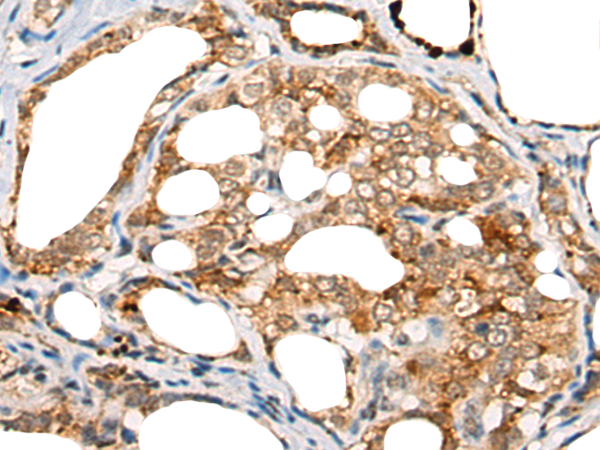

分类: 科研抗体货号: P13189别名: GAIP; RGSGAIP应用: IHC反应种属: Human, Mouse, Rat